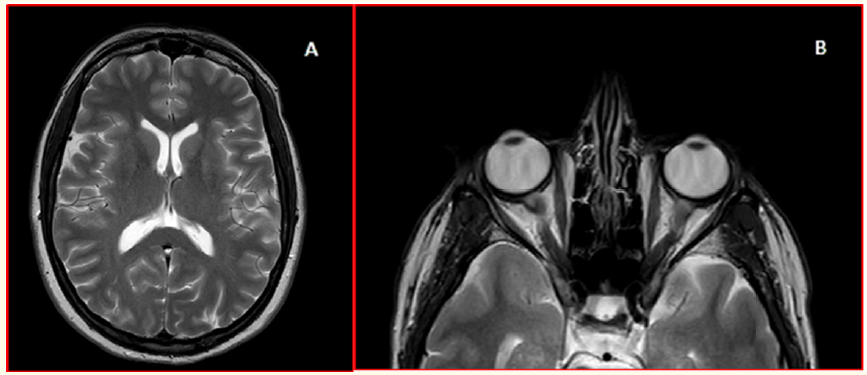

MRI Features of Brain and Spine in Patients Series with Mucopolysaccharidosis

Khadija Laasri, Abderrazzak Ajertil, Manal Jidal, Siham El Haddad, Nazik Allali, Abdeljalil El Quassar and Latifa Chat. 15(4): 53-69.